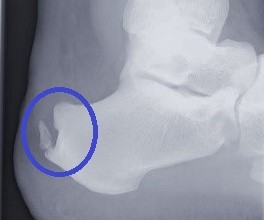

Achillessehnenbeschwerden sind ein Krankheitsbild, das in jeder fußchirurgischen Sprechstunde häufig auftritt. Nicht nur Ausdauersportler, sondern auch Patienten, die bei ihrer Arbeit lange stehen müssen, klagen über diese Probleme. Auslöser dieser Beschwerden kann die Haglund-Exostose (auch Haglund-Ferse genannt) sein, ist eine Formabweichung des Fersenknochens. Bei ihr ist der hintere obere Rand so stark ausgeprägt, dass es zu Schmerzen im Bereich der Achillessehne kommt.

Häufig kommt es neben der Haglund-Exostose zur Ausbildung eines dorsalen (an der Rückseite des Fußes liegenden) Fersenspornes. Hierbei verknöchert der Ansatz der Achillessehne am Fersenknochen. Es entsteht daraufhin eine schmerzhafte Vorwölbung am hinteren Rand des Fersenknochens.

Ein Röntgenbild des oberen Sprunggelenkes ist zur Darstellung der Haglund-Ferse und des dorsalen Fersenspornes ausreichend. Um zudem Einrisse der Achillessehne nicht zu übersehen, ist die Anfertigung eines MRT-Bildes sinnvoll.